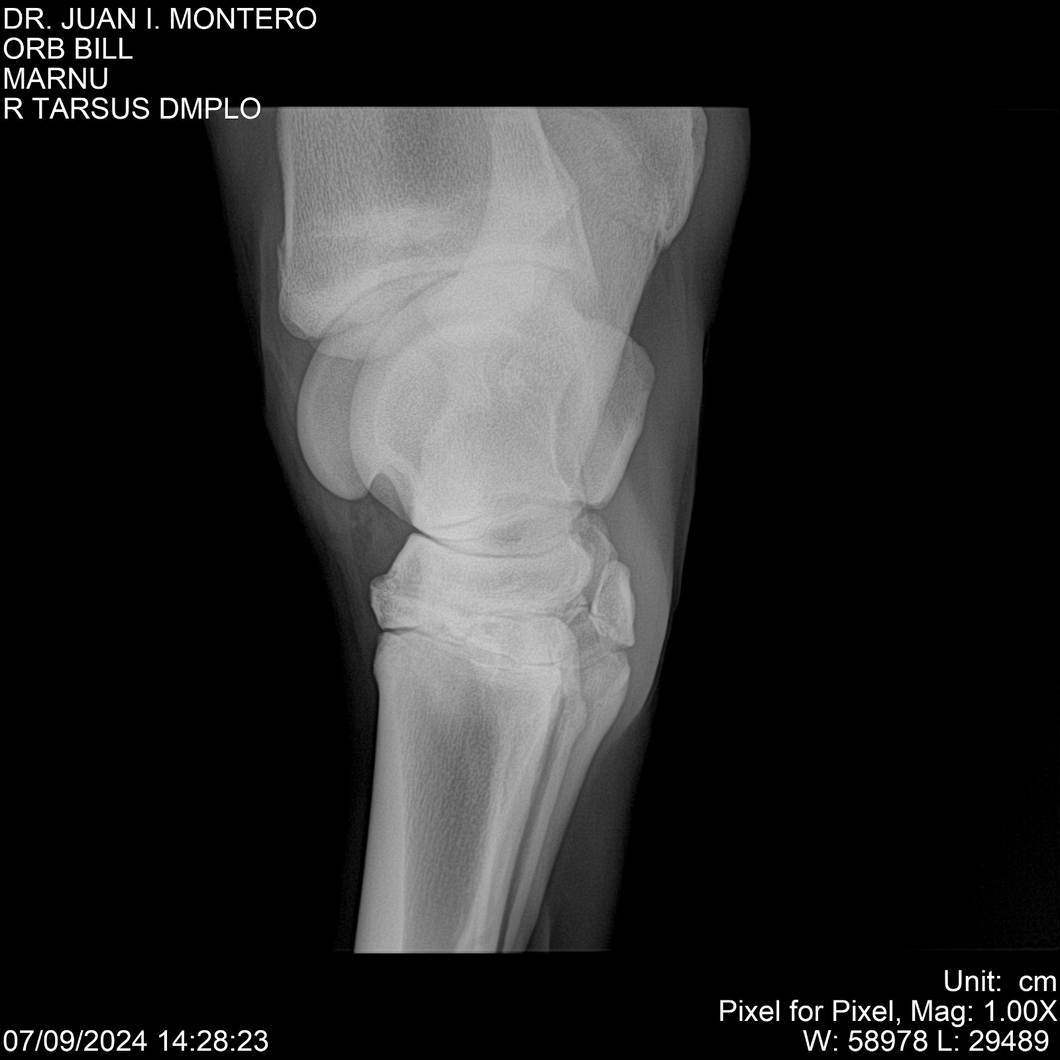

LOTE 7, ORB BILL 🔥 🔥 🔥 Lote Anterior Volver al remate Lote Siguiente Ficha Contacto Montevideo - Ficha del Lote Identificador: #282523 Categoría: Yeguarizos Montevideo - 83 Visualizaciones ClicData Contacto Empresa: Abelenda N. R., Walter Hugo Nombre*: Teléfono* : E-mail* : Mensaje Enviar Registrese gratis Este contenido Exclusivo está disponible sólo para usuarios registrados Ingresar